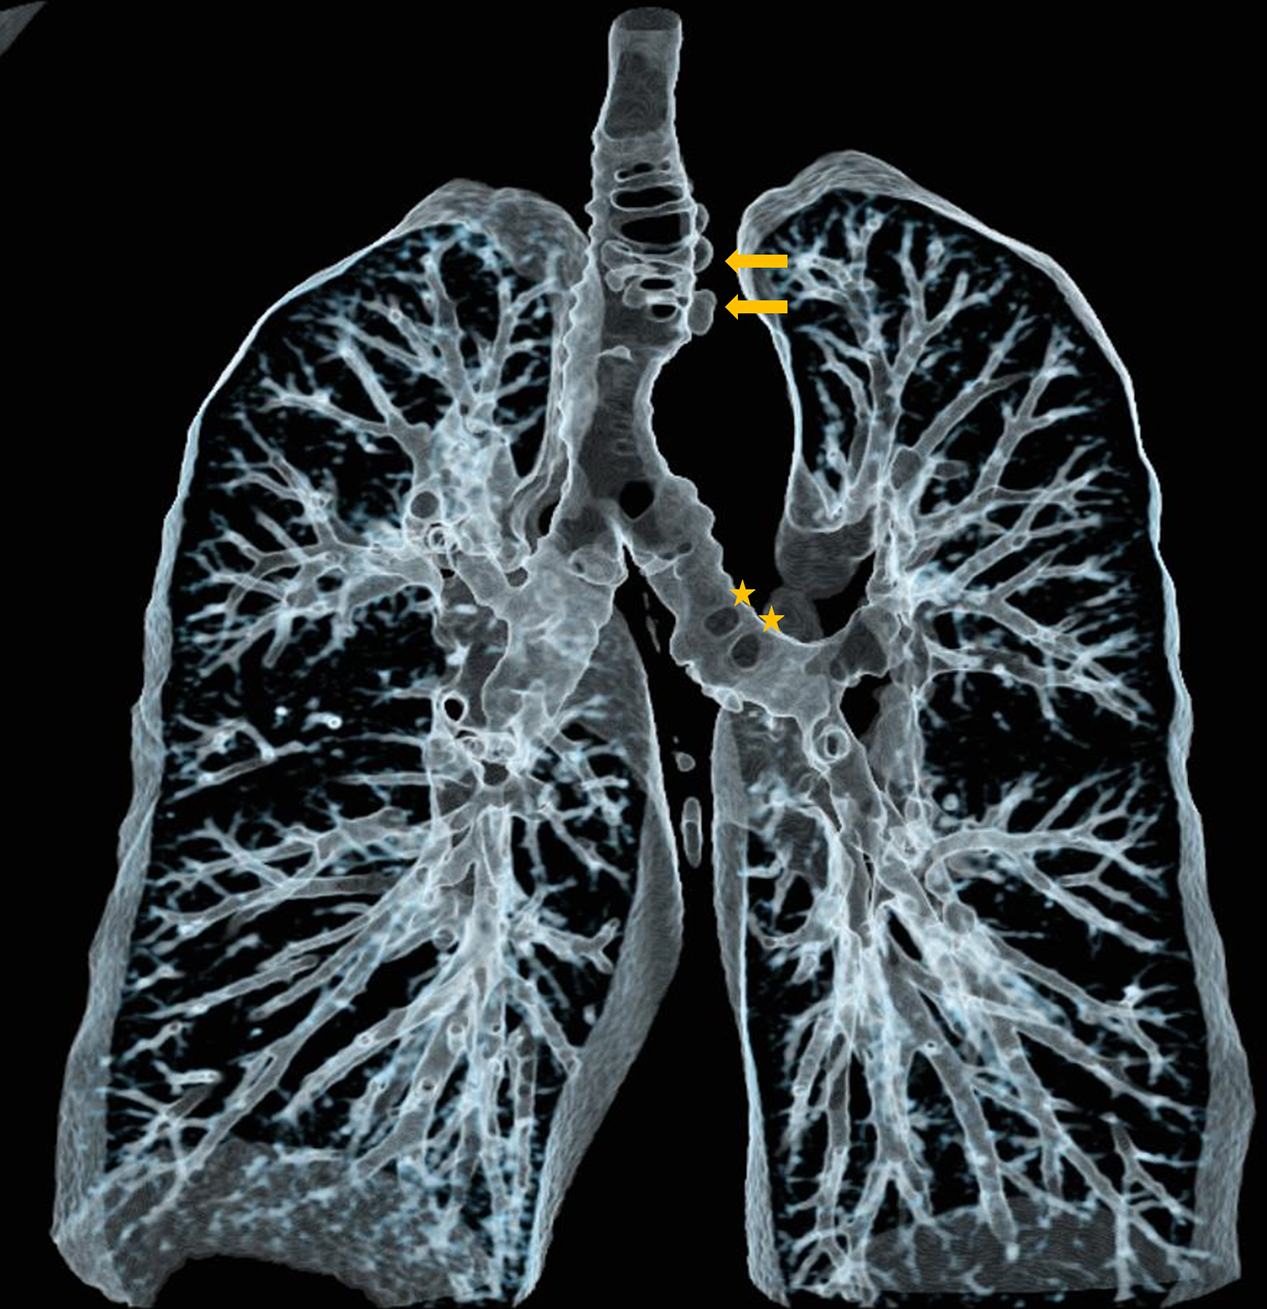

Volume rending technique (VRT) nicely illustrates the distribution of diverticula along the trachea and left main bronchus, as well as more distally in the bronchial tree (Figure 3).

Figure 3

Virtual bronchography of thacheobronchial diverticulosis.